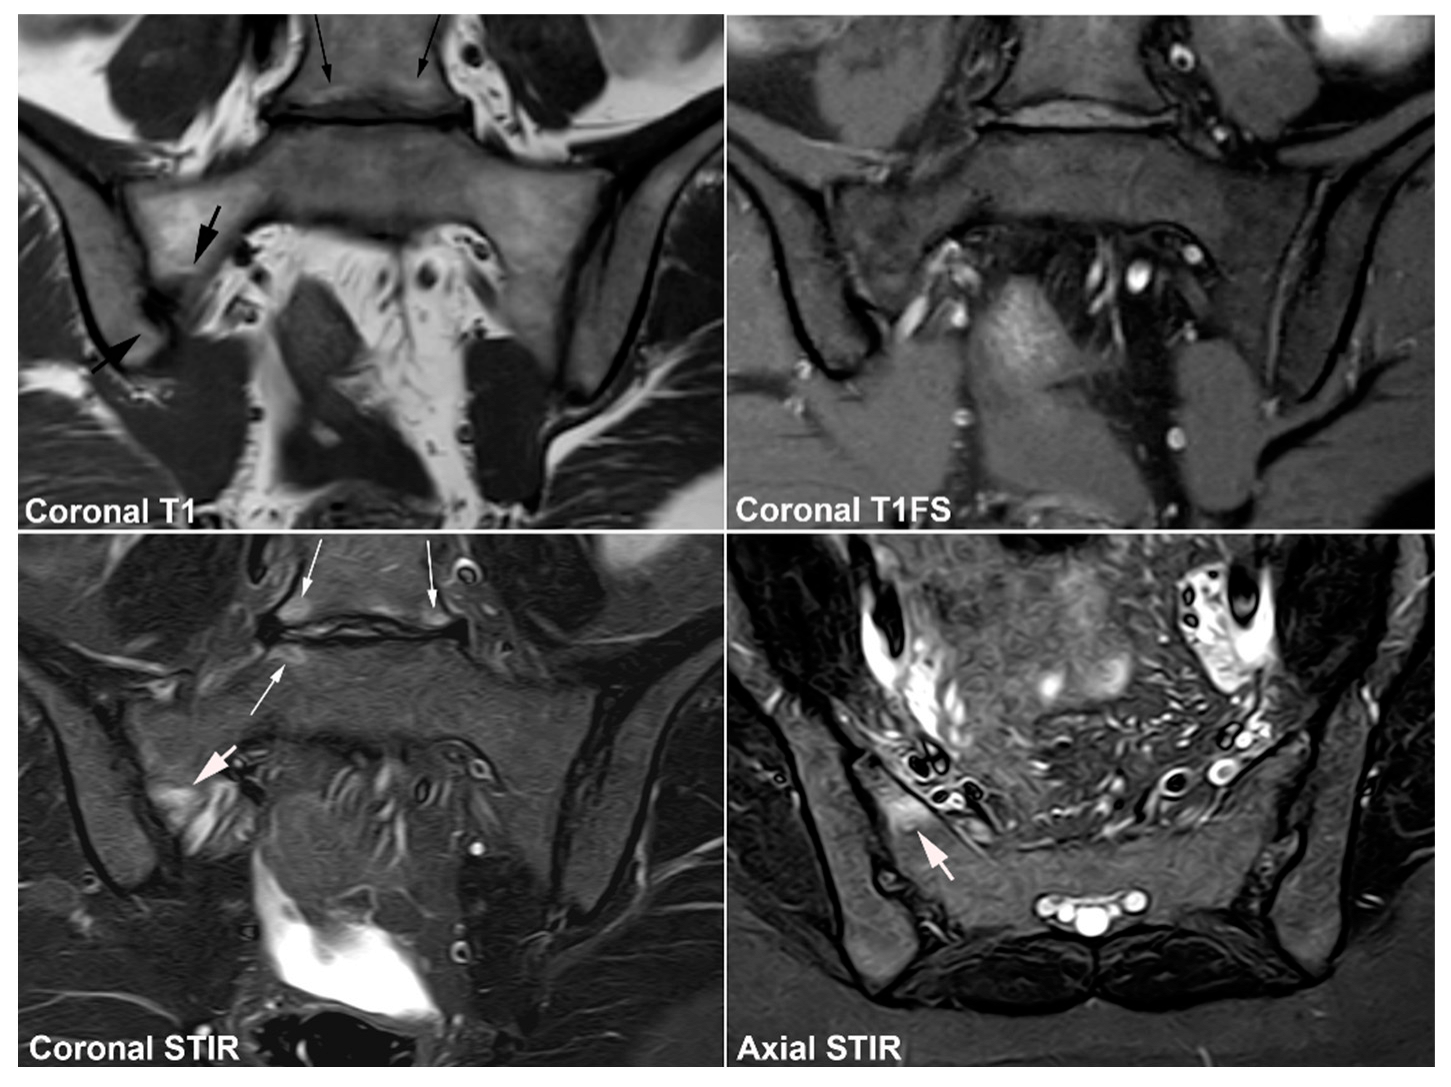

5.1. Osteitis Condensans ilii (OCI)

5.2. Pregnancy-Related Changes